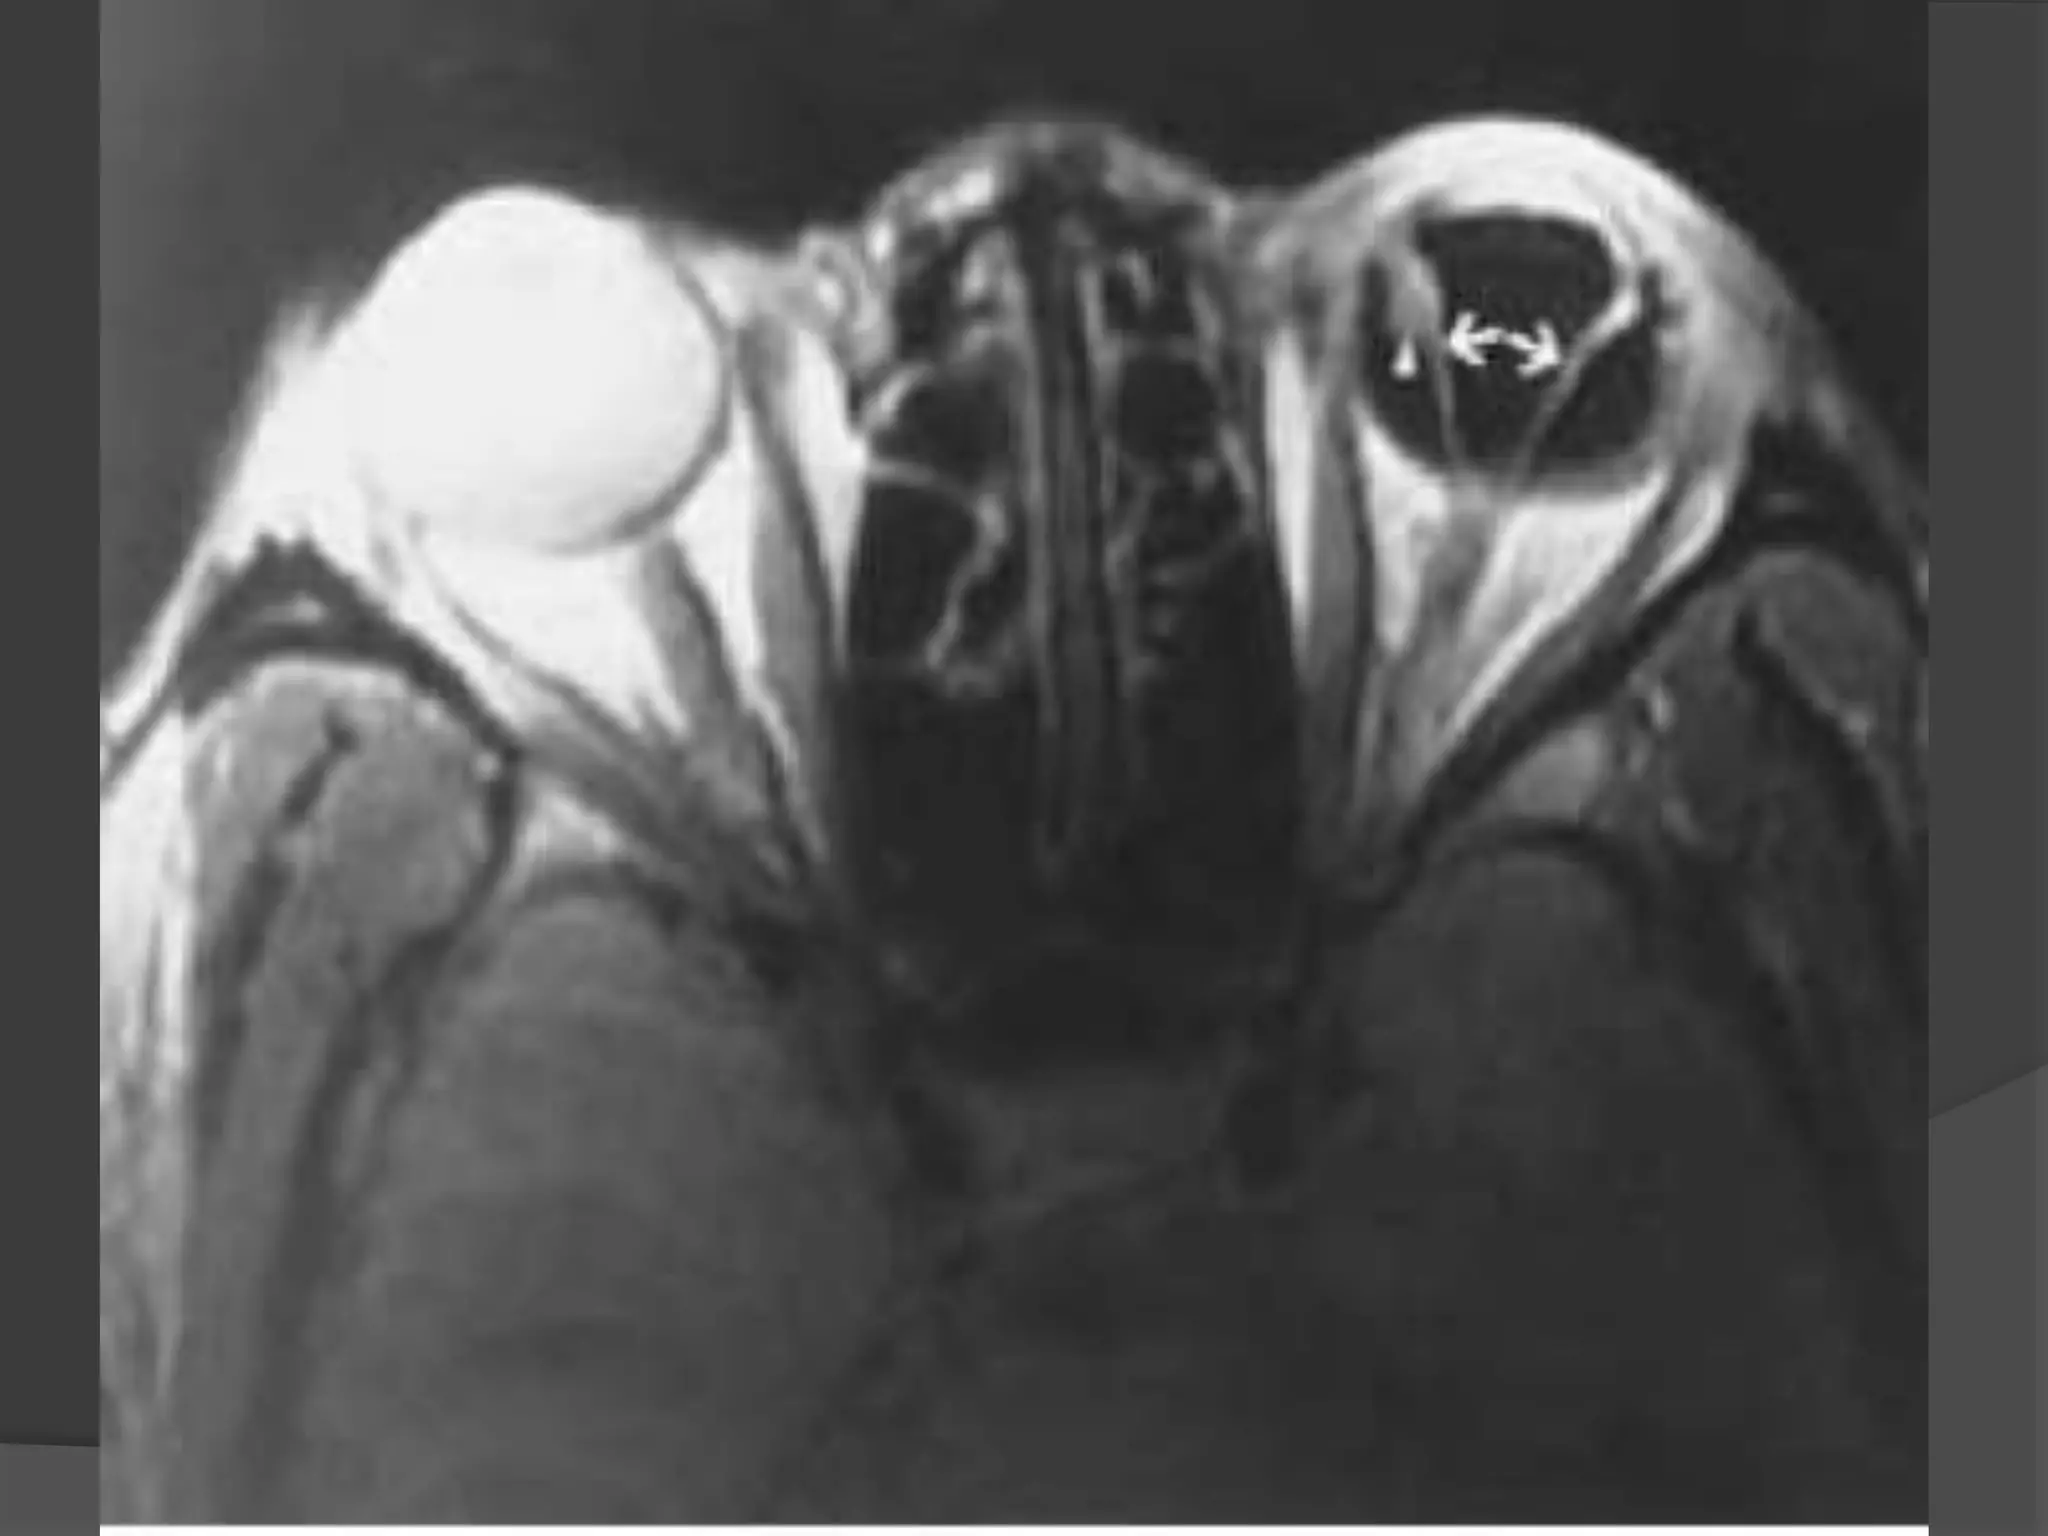

Cavernous Hemangioma. T1-weighted axial

(A) and sagittal (B) MR images demonstrate proptosis of right globe due

to well circumscribed, mid to high signal intensity intraconal mass.